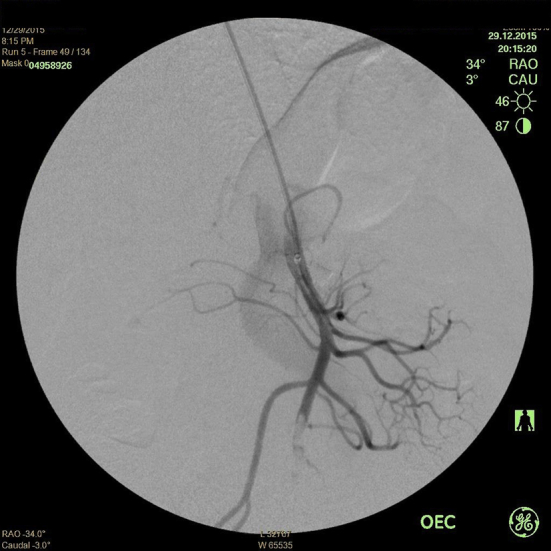

Figure 2.

Angiography showed an embolism of the superior mesenteric artery.